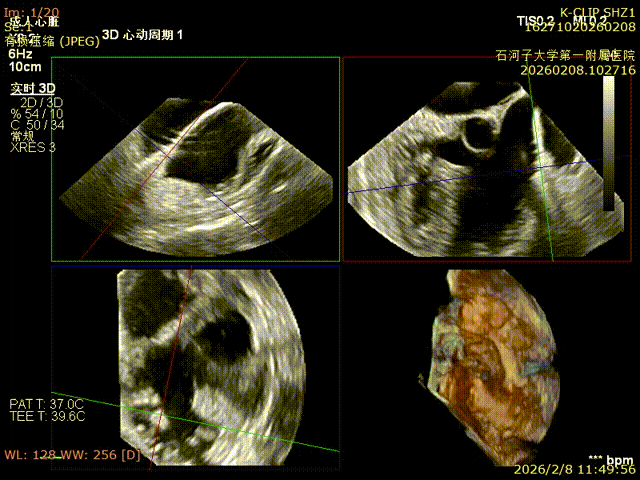

Preoperative anteroseptal regurgitation

Preoperative 3D view of regurgitation

Preoperative TTE: 4-chamber view regurgitation